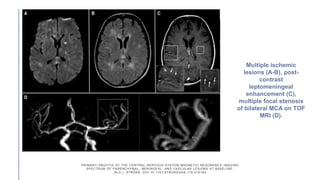

Multiple ischemic

lesions (A-B), post-

contrast

leptomeningeal

enhancement (C),

multiple focal stenosis

of bilateral MCA on TOF

MRI (D).